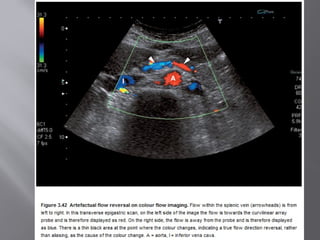

HEPATOPETAL/HEPATOFUGAL FLOW